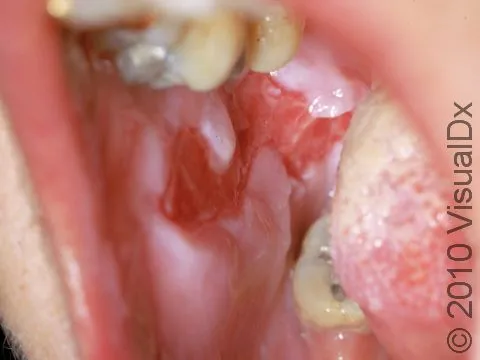

- Clinical: Flaccid blisters, common oral erosions, +Nikolsky sign.

| Oral Lesions | Common, initial | Rare/No |